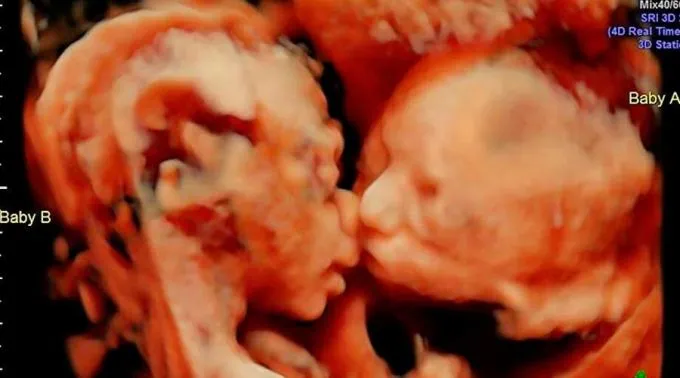

As gêmeas Isabella e Callie partilhando um gesto de carinho dentro do ventre / Foto: Instagram Carissa Gill

DENVER, 18 Abr. 17 / 06:00 pm (ACI).- Uma mulher norte-americana com 25 semanas de gravidez descobriu algo curioso quando fez uma ultrassonografia: viu suas gêmeas dando um terno beijo.

No início de abril, Carissa Gill foi com seu noivo, Randy Good, ao centro de ultrassom Fetal Vision, em Levittown, no estado da Pensilvânia. Ambos ficaram surpresos quando viram no ultrassom que as suas primeiras filhas, Isabella e Callie, estavam frente a frente e parecia que uma delas estava dando um beijo na outra.

O médico que fez o ultrassom, John Hamburg, expressou ao jornal ‘The Huffington Post’ que a imagem é verdadeira e que “fez cerca de 15 mil dessas, mas nunca havia visto dois gêmeos frente a frente como se estivessem se beijando. Normalmente, a cabeça de uma está em cima e a do outro em baixo”.